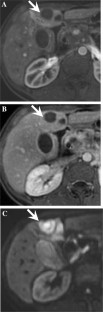

Fig. 3